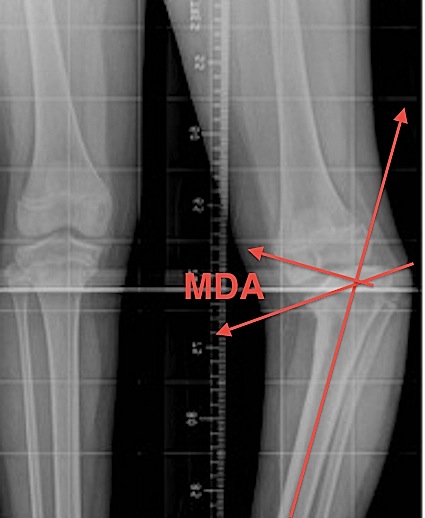

Metaphyseal - Diaphyseal Angle

Technique

- line drawn perpendicular to axis of tibia

- line drawn through medial & lateral beaks of metaphysis

- Blount's > 11°

- physiologic bow legs < 11°

Measurements

- 11° is arbitrary cut off where Blount's is more likely

- 16o definite